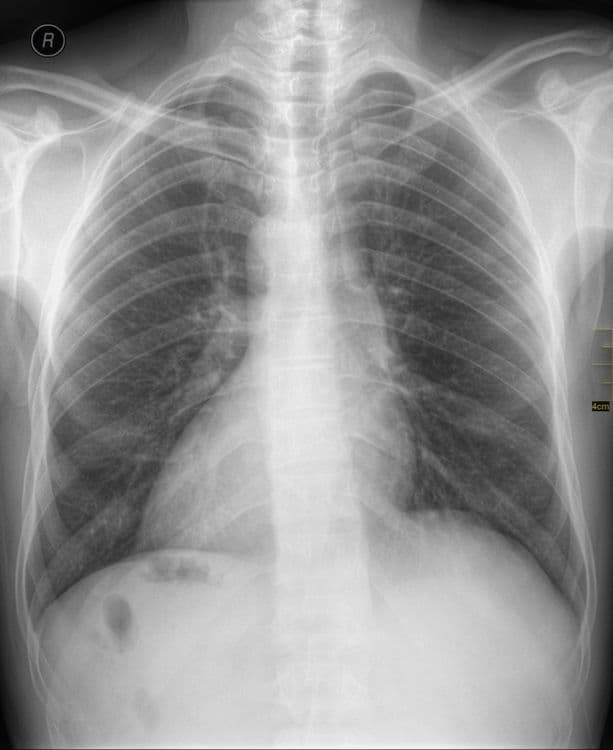

(हृदय उजव्या बाजूला)

जमालुद्दीन नावाचा हा माणूस नुकतंच पोटदुखीमुळे डॉक्टरांकडे आला होता. डॉक्टरांनी एक्स-रे काढल्यावर त्यांना धक्काच बसला. जमालुद्दीनच्या शरीरातील अवयव विरुद्ध बाजूला होते. त्याचं हृदय उजवीकडे आहे तर यकृत आणि पित्ताशय डाव्या बाजूला आहेत.